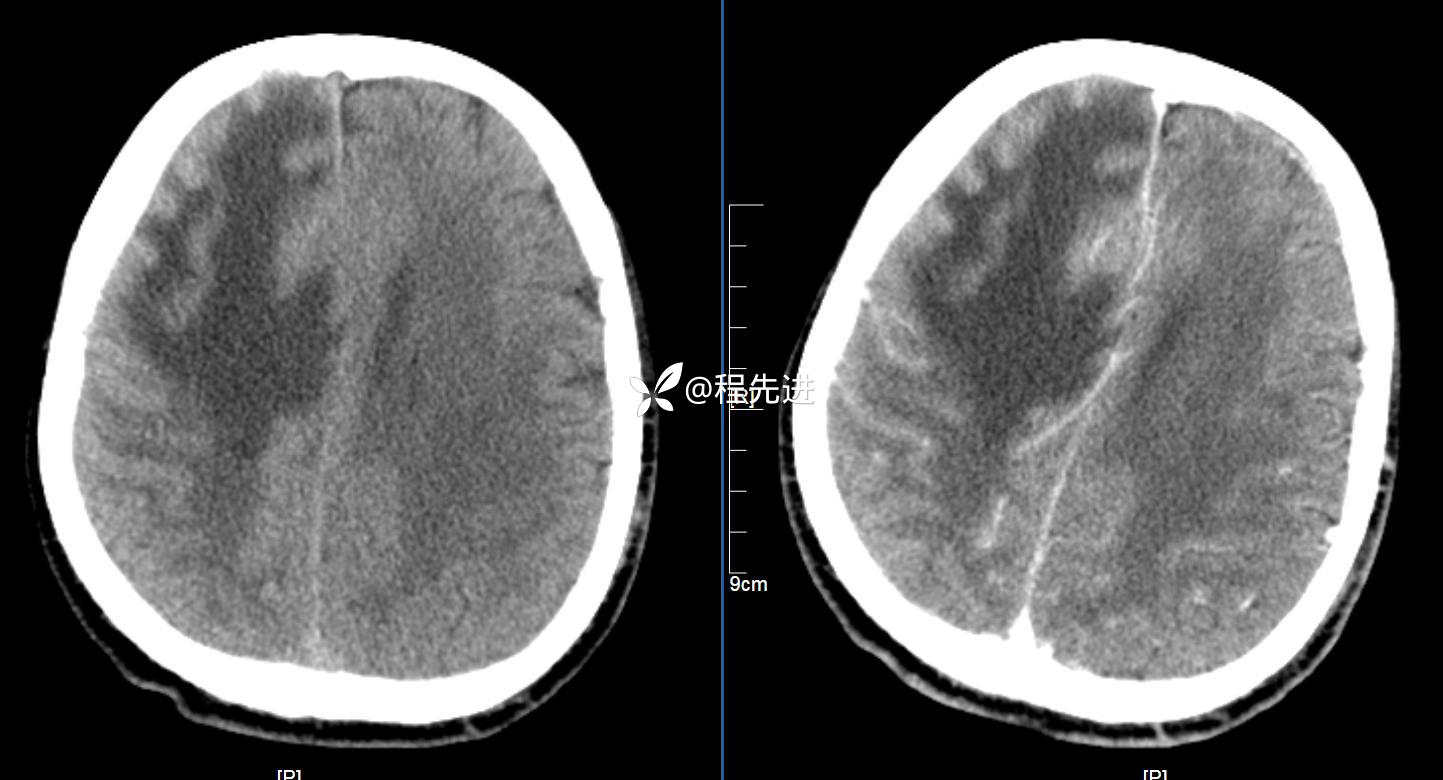

CT平扫+增强: